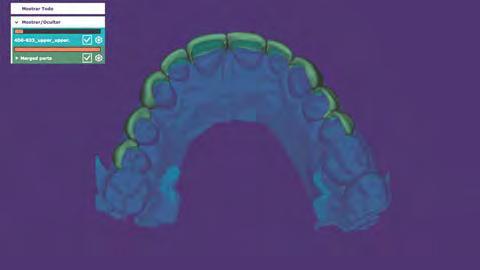

Protocolo Di gitalArch®️ 2.0: técnica de colocación, por el Dr. Luis Cuadrado Canals y cols.